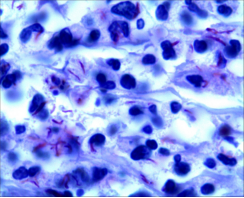

2.抗酸染色在结核病病理学诊断具有重要作用

一般情况病理石蜡组织切片,结核结节的坏死区中心或坏死区与上皮样肉芽肿交界处较容易查见抗酸菌,抗酸菌阳性对结核病诊断有重要的提示作用。